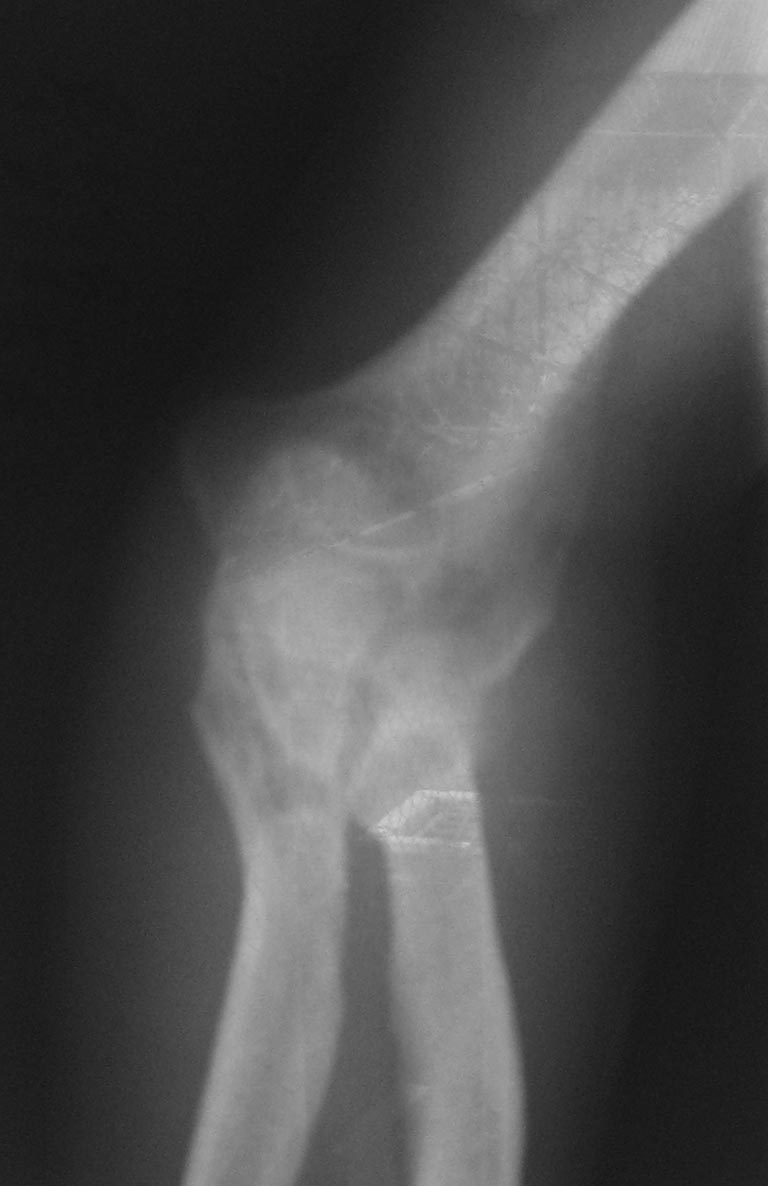

Лечения не было. Сейчас - контрактура и резко выраженный болевой синдром, в т.ч. вследствие давления trohlea humeri изнутри на кожу.

Качество первых двух снимков очень плохое. А на двух последних, по моему, перелом локтевого отростка. Если так, то просто остеосинтез

Локтевого отростка и передней стенки локтевой кости

Кроме КТ бывают обычные стандартные рентген-снимки, боковой проекции у Вас нет, потому и не знаете, как поступить с этим переломом локтевого отростка.